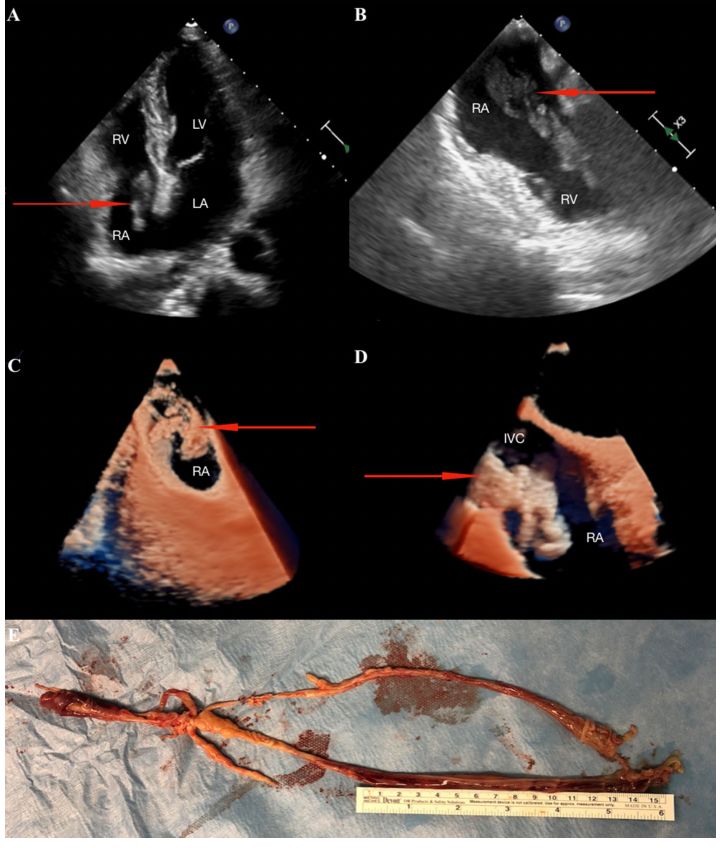

患者为一位39岁的女性,因怀疑右心房有额外肿块而入院。两周前接受了切除子宫和膀胱肿瘤的手术。经胸超声心动图证实RA中存在不均匀和可移动的肿块(图1A)。此外,下腔静脉(IVC)也受累。

图1: A: 二维四腔视图;B:二维双腔视图;C-D三维真实感成像;E去除RA和下腔静脉的结构。箭头显示RA和IVC的肿块

研究者决定进行经食管超声心动图(TEE)检查,结果显示该结构在整个心动周期内都突出于三尖瓣(图1B)。使用最新的显示方法,Philips心脏TrueVue 3D逼真成像,可以详细地看到一个长形、可移动、不均匀的巨大肿块,与心脏壁和静脉无粘连,并随着心跳振动(图1C-D)。

患者接受了手术,在心脏跳动的情况下,通过RA通过体外循环切除了一个长约30厘米的巨大肿块(图1E)。术后病理检查诊断为平滑肌瘤病。三维真实感成像的使用不仅可以更好地直观地识别病理结构,而且可以更详细地规划手术过程。与3D-echo相比,它的主要优点是能够移动虚拟光源,从而可视化心脏的特定部分,特别是心脏的人工瓣膜和其他肿块。